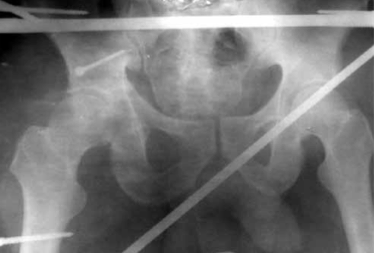

В случае отказа больного от аппарата внешней фиксации или при противопоказаниях производится скелетное вытяжение сроком 3-4 недели. Когда отломок проецируется на уровне или ниже ориентирной линии (рис. 4), разрез производится на 1 см ниже ее. Также тупо разводятся волокна большой ягодичной мышцы.

Рентгенография тазобедренного сустава до и после вправления. Перелом среднего отдела заднего края вертлужной впадины со смещением

Большая, средняя и малая ягодичные мышцы вместе с грушевидной отводятся кверху, верхняя близнецовая — книзу. Следует помнить о выходе из малого таза седалищного нерва под грушевидной мышцей в проксимальном ее участке. Также производится ревизия состояния хряща головки бедренной кости, отломка, установка его после промывания полости сустава, стабильная фиксация с элементами компрессии (рис. 5, 6).

Обзорная рентгенограмма таза. Состояние после открытой репозиции и фиксации среднего отдела заднего края вертлужной впадины 2 винтом. Стабилизация и разгрузка тазобедренного сустава в аппарате внешней фиксации

Рентгенография тазобедренного сустава в двух проекциях (прямая и аксиальная). Срок после оперативного лечения — 3 года